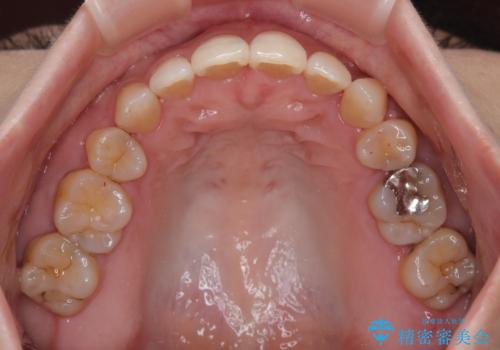

- 前歯のデコボコと口元の突出感を気にして来院された患者様です。

上下前歯がくちばしのように突出していたため、上下左右の第一小臼歯4本を抜歯し、ワイヤー装置にて矯正治療を行うこととしました。

上顎骨に対して下顎骨がやや前方位に位置しているため、歯肉退縮を回避するために下顎前歯をあまり内側に移動させることができない状況でしたが、十分に口元の突出感を改善することができました。